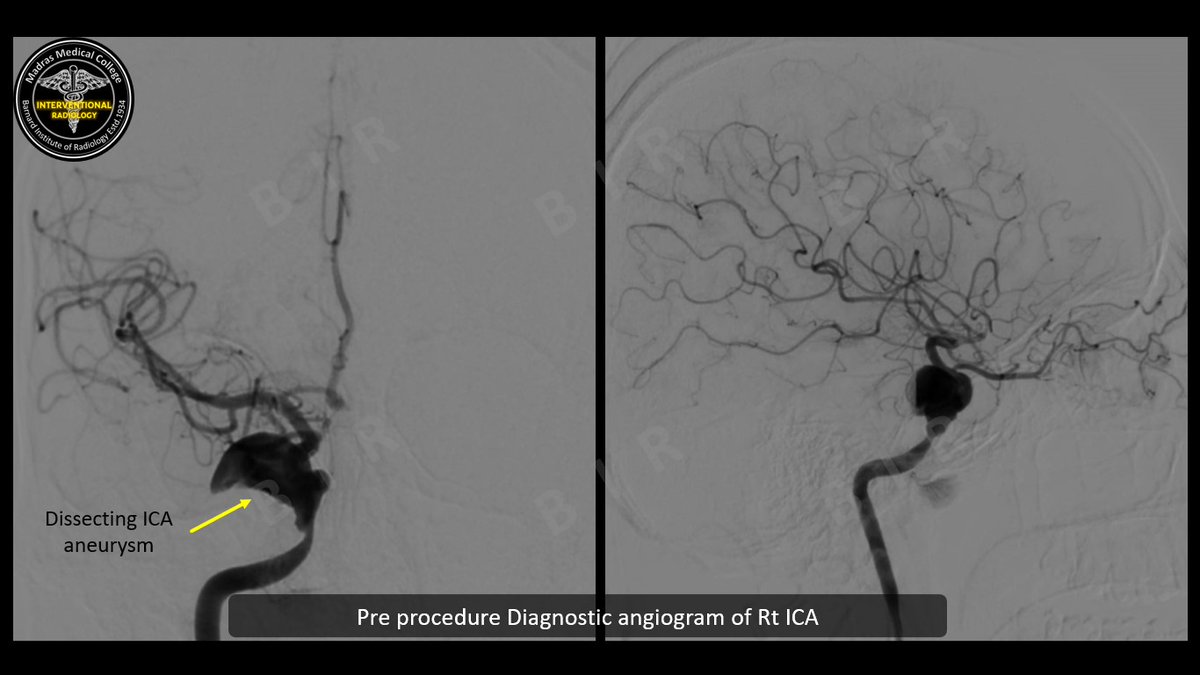

Ca retromandibular trigone>Massive per oral bleed>IMA blowout>#justglueit #irad #MedTwitter @ISVIRIndia @cirsesociety @SIRspecialists @karananandpara @PulkitRangarh @Murthy_CS_ @ChengaziMD @DrAjityadav @keithppereira